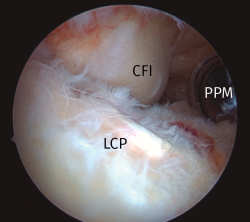

Figura 1. Imagen del compartimento posteromedial desde una visión transescotadura desde el portal anterolateral, rodilla derecha. Se evidencia la presencia de un cuerpo libre “oculto”. CFI: cóndilo femoral interno; CL: cuerpo libre; RPMI: rampa posterior de menisco interno.

Figura 9. Abordaje transeptal, rodilla izquierda. Visión desde el portal posterolateral tras la resección del septo posterior. Visión sin limitaciones de los compartimentos posteriores. Se aprecia la parte posterior del cóndilo femoral interno, la inserción tibial y el margen craneal del LCP y la cánula de trabajo en el portal posteromedial. LCP: ligamento cruzado posterior; CFI: cóndilo femoral interno; PPM: portal posteromedial.